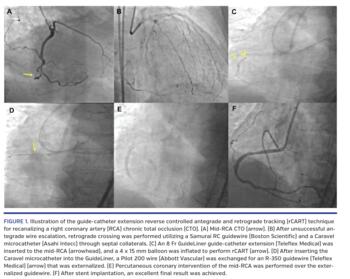

During the retrograde approach, guidewire crossing can occur from the distal to the proximal true lumen (true-to-true retrograde wire crossing) or from the proximal to the distal true lumen (“just marker” technique, in which the retrograde guidewire serves as a marker of the distal true lumen position, helping to direct antegrade guidewire crossing). In most cases, however, either the antegrade or the retrograde guidewire enter the subintimal space, requiring re-entry into the true lumen, which is most commonly achieved by inflating a balloon over the antegrade guidewire, followed by advancement of a retrograde guidewire into the proximal true lumen (the reverse controlled antegrade and retrograde tracking [rCART] technique).4,10-12 A modification of the rCART technique is use of a guide-catheter extension through the antegrade guide catheter that serves as a target for the

retrograde guidewire.13,14 This technique is illustrated in Figure 1. We used a contemporary multicenter CTO-PCI registry to determine the frequency and outcomes of guide-catheter extension rCART.